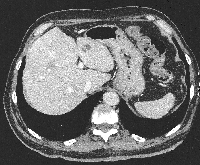

Πρόκειται για άνδρα ασθενή 67 ετών που διαπιστώθηκε ότι έπασχε από αδενοκαρκίνωμα του σιγμοειδούς με 6 συνολικά ηπατικές μεταστάσεις αμφοτερόπλευρα (εικόνες 1, 2). Η διενέργεια PET-CT δεν ανέδειξε εξωηπατική νόσο. Δεδομένου ότι ότι η πρωτοπαθής εστία δεν προκαλούσε αποφρακτικά φαινόμενα και εξαιτίας του εξαιρετικά μεγάλου καρκινικού φορτίου του ήπατος σε σχέση με αυτό το εντέρου, αποφασίστηκε η αντιμετώπιση πρώτα των μεταστάσεων ("liver first" approach). Σύμφωνα με την ανάλυση MeVis (εικόνα 3) η αριστερή ηπατεκτομή οδηγούσε σε 69% ηπατικό υπόλειμμα ενώ η αριστερή εκτεταμένη ηπατεκτομή οδηγούσε σε 28% ηπατικό υπόλειμμα (τριχασμός πυλαίας). Με βάση αυτά τα δεδομένα αποφασίστηκε η κάθαρση του ήπατος από το μεταστατικό φορτίο με ηπατεκτομή και σύγχρονη εστιακή καταστροφή με ραδιοσυχνότητες. Αρχικά, ο ασθενής υποβλήθηκε σε 8 κύκλους χημειοθεραπείας (Avastin, FOLFOX). Ακολούθησε αριστερή ηπατεκτομή, δύο σφηνοειδείς ηπατεκτομές (εικόνα 4) και εστιακή καταστροφή με ραδιοσυχνότητες του παρεγχύματος στο όριο των τμημάτων 5/8 (εικόνα 5), παρεμβάσεις που έφεραν την πλήρη κάθαρση του ηπατικού μεταστατικού φορτίου. Κατόπιν, ο ασθενής υποβλήθηκε σε ακόμα 4 κύκλους χημειοθεραπείας. Η ογκομέτρηση την 4η μετεγχειρητική εβδομάδα ήταν ικανοποιητική (εικόνα 6). Ακολούθως, ο ασθενής υποβλήθηκε σε σιγμοειδεκτομή. Τελικά, η χημειοθεραπεία ολοκληρώθηκε με άλλους 6 κύκλους. Ο ασθενής εξακολουθεί να παραμένει ελεύθερος νόσου στους τακτικούς ελέγχους (δις ετησίως) με κολονοσκοπήσεις και CT.